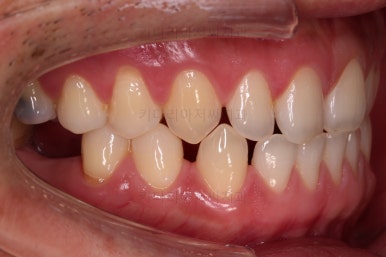

거의 모습이 완성되었습니다.

교정치료도 종료 되었고 연산동임플란트 잘 완성이 되었어요.

총 14개월이 걸린 치료였는데 비교적 짧은 기간 내에 틈새도 모으고, 임플란트 및 충치치료도 다 완료를 할 수 있었습니다.

전후 사진을 비교해 볼게요.

비교적 짧은 시간 안에 환자분이 만족하는 치료를 할 수 있었어요.